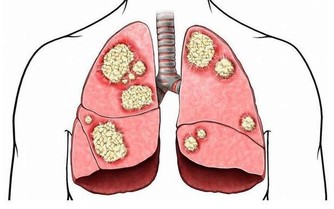

病理性小便分叉是由疾患引起的,除前列腺增生外,其他疾病如急性尿道炎或急性前列腺炎,由於尿道充血、腫脹,分泌物增多,也會導緻小便分叉。

損傷或炎症導致的尿道狹窄,如尿道內的損傷或損傷後的繼發感染、反復發作的尿道炎等,造成尿道內膜組織形成瘢痕,使局部尿道管腔變得狹窄,尿液排出不暢,同樣會出現小便分叉。